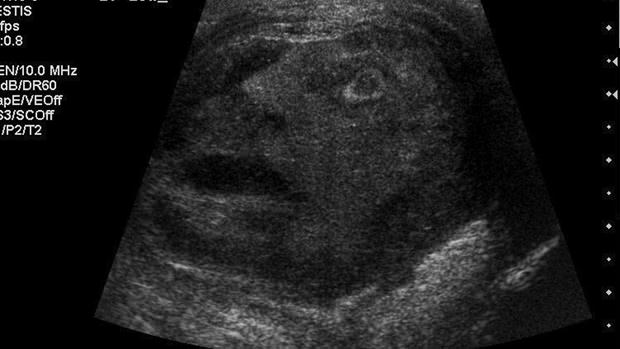

Wednesday- Doctors in Queen's University Kingston Ontario have spotted what looks like the face of a screaming man in an altrasound scan of cancerous tumour.

According to fp news the patient from whom the picture was emerges was not told about the abnormal sighting.

The strange sighting has of late being compared to other similar sightings like that of the virgin mary appearing on toast or grilled cheese sandwiches.